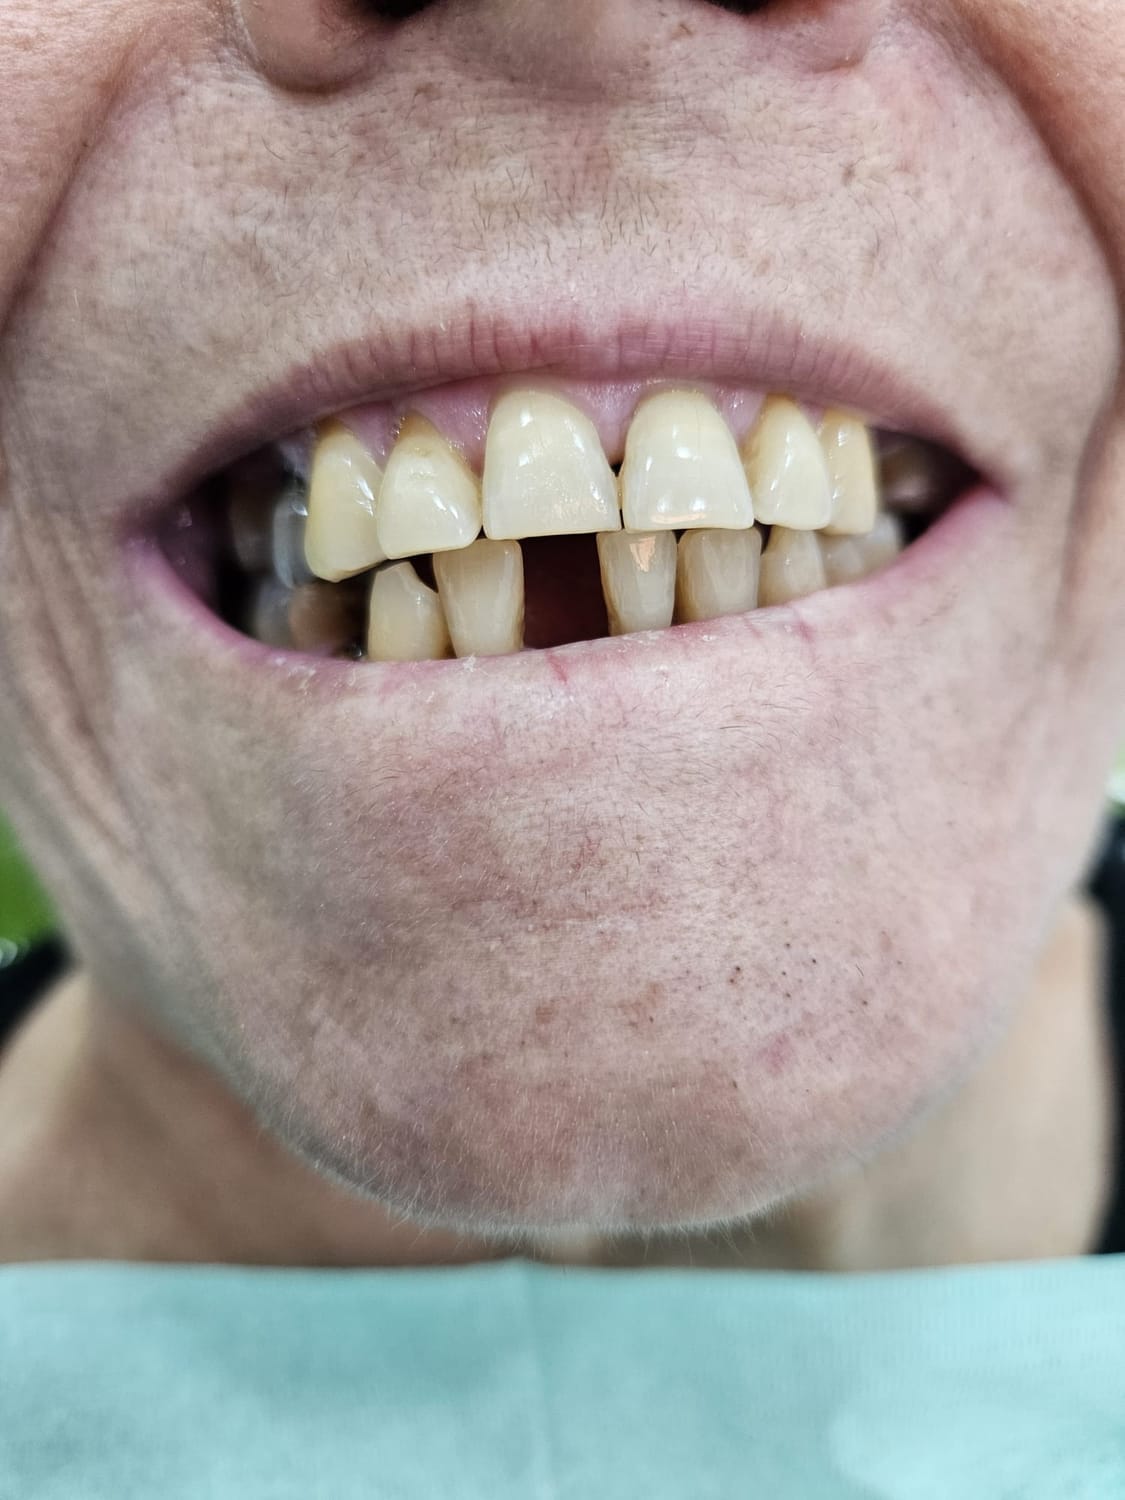

Paziente affetto da atrofia grave con parodontite acuta localizzata.

Caso progettato e realizzato attraverso la tecnica dell'implatologia computer-guidata con impianti short.

Grazie ad una progettazione fatta mediante PC su tac otteniamo preventivamente dove posizionare gli impianti la lunghezza la larghezza e la corretta angolazione di inserimento che ci consente di realizzare le protesi ancora prima di farevlintervento e di evitare tagli e scollamento gengivali che provocano dolore e bruciore riducendo notevolmente itempi di guarigione e i fastidi post intervento